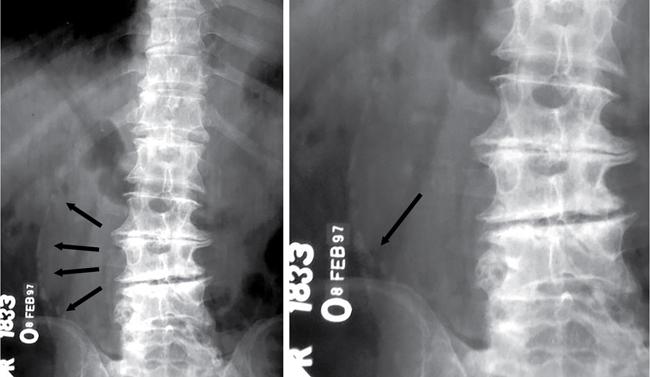

UNDERSTANDING THE ADULT ABDOMINAL RADIOGRAPH: TECHNIQUES AND INTERPRETATION Tanvi Modi Radiography of the abdomen is a common practice for the evaluation of abdominal organs. The anatomy and pathology of digestive, hepatobiliary and genitourinary systems can be assessed using radiographs, either as a stand-alone practice or as a primary imaging modality followed by contrast studies, ultrasound or cross-sectional imaging. In addition, abnormalities of the musculoskeletal or integumentary system can also be deduced on the basis of abdominal radiographs. This chapter intends to give an overview on the techniques and positioning in abdominal radiography as well as interpretation of normal and abnormal features. While superior imaging modalities such as ultrasound, computed tomography (CT), magnetic resonance imaging, capsule endoscopy and the likes have taken over abdominal imaging by and large, radiography still holds a pivotal role in certain situations and conditions, such as: The standard abdominal radiograph is taken in supine position and anteroposterior projection. This is also popularly known as the KUB (kidneys-ureters-bladder) radiograph. Previously, supine as well as erect radiographs were performed in all patients; however, this is not commonly done due to high-radiation dose. For all indications of abdominal radiography, including acute abdomen, supine radiographs are sufficient in terms of radiographic diagnosis, with the exception of perforation for which an erect chest or lateral decubitus radiograph can be performed if there is clinical suspicion. Patient should lie supine on the imaging table with median sagittal plane at right angles to the table and coincident with the midline of the table (Fig. 7.1.1.1). The body is divided into equal right and left halves by the median sagittal which passes through the sagittal suture of the skull. Pelvis should be adjusted so that the anterior superior iliac spines are equidistant from the table top. Gonadal shields, in the case of male patients, should be placed with the upper edge of the shield at the level of pubic symphysis. Although rarely used for female patients, these should be positioned between the anterior superior iliac spines and the pubic symphysis. The centre point of the image receptor should be approximately located at a point 1 cm below the line joining the iliac crests. The X-ray beam should be in a vertical direction, perpendicular to the table top and image receptor at the centre point. Collimation should be such that the soft tissue and subcutaneous region along lateral aspects of the abdominal cavity should be covered within the image. Also, the superior extent involving diaphragm and inferior extent involving the inferior pubic rami is important to look for any lower chest pathologies or any inguinal hernia. 35 × 43 cm (14 × 17 inches) in portrait orientation. On an average, abdominal radiograph exposes a patient to a dose of approximately 1.5 mSv, which is equivalent to 75 chest radiographs or 1/6th dose of a standard CT of the abdomen. The entrance skin dose is approximated to be 4 mGy. At such an effective dose, the additional lifetime risk of fatal cancer is 1 in 30,000. The exposure time is kept short. Patient is asked to exhale completely and hold their breath, with exposure taken at this point of full expiration to ensure imaging of abdominal organs in their natural positions. Modifications of this technique can be made depending on patient habitus and clinical condition. Kilovoltage peak (kVp) should be set to allow adequate visualization of abdominal soft tissue structures as well as semiopaque renal and biliary calculi. Average kVp is set at 70–85 kV. 102 cm (40 inches) Grids are commonly used to reduce scatter radiation. Placement of side marker on the image receptor at the time of radiographic exposure is essential. Bowel pattern depiction should be such that there is minimal lack of sharpness. Standard guidelines for abdominal radiography dictate that the radiograph should extend from the diaphragm up to the level of inferior pubic rami and must include the lateral abdominal wall musculature. The abdomen is divided into four quadrants on the basis of two perpendicular lines (Fig. 7.1.1.7). The vertical line passes through the mid sagittal plane and crosses the umbilicus and symphysis pubis. The horizontal line is a transverse line across the umbilicus at 90 degrees to the vertical line and is situated at the level of L4–L5 intervertebral disc. The quadrants are as follows: Another division system is dividing the abdominopelvic cavity into nine regions using two vertical and two horizontal planes (Fig. 7.1.1.8). The vertical planes, also known as the right and left lateral planes, are parallel to the midsagittal plane between midline and anterosuperior iliac spines on either side. Of the two horizontal planes, the upper transpyloric plane is at the level of lower border of L1 and the lower transtubercular plane is at the level of L5. The nine regions are: On a standard radiograph, the exposure should be such that the stomach, bowel loops, outlines of liver, spleen, kidneys, psoas muscles should be well identified. Also, lumbar transverse processes should be seen. Arch of the pubic symphysis should be visible to evaluate bladder region. A well-centred film without rotation will demonstrate bilaterally symmetrical lower ribs, iliac wings, ischial spines and obturator foramina. Different structures seen on an abdominal radiograph can be classified into five basic densities: Identification of different structures depends on the relative degree of contrast between their densities. The demarcation is clearer in chest and is diminished in abdomen due to relative similar soft tissue density of various structures. On a normal radiograph, relatively large amounts of gas in stomach and colon with minimal small bowel gas can be seen. Further, colonic gas can vary from negligible to extensive, mimicking obstruction pattern; however, usually the gas is enough to delineate colonic haustral pattern. Faecal matter gives a mottled appearance to colonic gas. Short-air fluid levels on an erect radiograph may be seen even in normal cases. The normal appearance of small bowel loops on an abdominal radiograph follows the rule of threes: Stomach is seen in the left upper quadrant and is visualized when distended with air. It is commonly seen extending from T11 to L2 level. Common feature identifying the stomach is the fundal gas which is usually seen as an air fluid level within the gastric lumen. Small bowel loops are distributed to the centre of the abdominal cavity and large bowel loops are peripheral. Duodenum is predominantly situated in right upper quadrant. It extends to left upper quadrant in the region of duodenojejunal flexure. Jejunum occupies the left upper and lower quadrants and is easily identified due to the presence of thick, numerous, closely spaced valvulae conniventes (Fig. 7.1.1.9A). The ileum occupies both lower quadrants and extends into right upper quadrant. Ileum has few and less prominent valvulae as compared to jejunum (Fig. 7.1.1.9B). Ascending and descending colon are retroperitoneal and have relatively fixed positions along lateral aspect of the abdominal cavity on either side. Transverse and sigmoid colon, on the other hand, may have a variable position due to their mobility along mesocolon and redundant pattern. These can be identified with confidence on account of haustrations and faecal matter (Fig. 7.1.1.10). Haustrations are usually well seen in ascending and transverse colon and poorly delineated beyond splenic flexure. Caecum is in the right lower quadrant, though it may be mobile or pulled up. Rectal gas is usually seen in the midline at the level of pelvis and its presence rules out large bowel obstruction. All these positions may vary due to anatomical conditions such as malrotation or pathological conditions, for example volvulus. Liver, spleen and renal outlines cannot be completely traced with precision due to the overlap by bowel loops. On a frontal projection, the liver appears as a triangular structure occupying right and left hypochondrium and epigastric region. Occasionally, the right lobe may be seen extending lower than the right renal shadow. This is a normal variant known as Reidel’s lobe. Gall bladder is situated in the posterior and inferior region of the liver and any pathology of the gall bladder should be looked for in this region. On a lateral radiograph, the gall bladder is anterior to the midcoronal plane. This helps in distinguishing gall bladder calculi from renal calculi, which will be more posteriorly situated. Spleen is seen in left upper quadrant/left hypochondrium, flushed to left lower ribs and left hemidiaphragm. Pancreas is present in the epigastric region (right and left upper quadrants) and is usually not identified in the absence of a pathology. The kidneys are bean-shaped retroperitoneal organs which are seen on either side of the vertebral column and lateral to psoas muscles. Due to the presence of liver on the right side, this kidney is slightly lower in position as compared to its contralateral counterpart. The visualization of kidneys on radiographs is facilitated by the surrounding fatty capsule. Kidneys lie between T11–12 and L2 level, with left kidney 1 cm higher than the right. Psoas muscle shadow can be normally seen along lateral aspect of lumbar spine bilaterally and is mildly concave (Fig. 7.1.1.11). Abdominal wall muscles are not routinely assessed on radiography; however, inclusion of lateral abdominal wall (muscles as well as subcutaneous plane) is a must while performing radiography. The flank stripe or the properitoneal fat stripe is a fat density linear concavity seen along lateral abdominal wall (Fig. 7.1.1.11). It is bound by the paracolic gutters and air-filled ascending and descending colon. All the solid organs in the abdomen are identified due to the fat density outlining them. Distortion of these fat lines helps in identifying organomegaly or focal mass lesions. The dome of urinary bladder is outlined by fat, which aids in differentiating its density from other soft tissue structures of the pelvis. Not all calcifications seen on abdominal radiograph are abnormal. Some may depict age-related changes such as vascular calcifications involving abdominal aorta, pelvic vessels, splenic artery in the region of left upper quadrant. Within the pelvis, phleboliths may be seen and mistaken for urinary calculi. Assessment of lumbosacral spine, iliac bones and femoral heads can be made on the basis of plain radiography. Degenerative changes may be commonly seen. Lower ribs can also be evaluated for pathologies. Dilated small bowel loops with rounded soft tissue density in midline over umbilical region suggests obstruction secondary to umbilical hernia. Pneumoperitoneum must be looked for in all cases of acute abdomen. While erect chest and left lateral decubitus radiographs can detect even 1 mL of free air, there are multiple signs on supine radiograph to suggest this diagnosis, for example Rigler’s sign, falciform ligament sign, football sign (Figs. 7.1.1.24 and 7.1.1.25). Retroperitoneal perforation may demonstrate air outlining psoas muscles and retroperitoneal organs. Small amount of free air may persist in the abdominal cavity up to 3 weeks after surgery, although it usually resolves within a week. Clinical history is important in such cases. Air foci within the bowel wall may represent bowel ischaemia/strangulation. Linear gas patterns in right hypochondrium may be due to two causes, that is pneumobilia and pneumoporta. The former can be seen normally postbiliary surgery, sphincterotomy, ERCP or in the case of abnormal fistulous communication between bowel and biliary tree (Fig. 7.1.1.26A). Pneumoporta (Fig. 7.1.1.26B) is a red flag and warrants further investigation to look for conditions such as mesenteric ischaemia and toxic megacolon. Pneumobilia is more centrally located whereas air shadows in pneumoporta are seen reaching up to periphery of liver. Air foci over renal shadows (Fig. 7.1.1.27), gall bladder or pancreas, in the absence of recent procedural history, suggest fulminant infection and mandate urgent intervention. Central midline calcific foci between T9 and T12 vertebrae can be attributed to calcific pancreatitis (Fig. 7.1.1.28). In the left upper quadrant, areas of calcification seen involving a shrunken spleen may be seen in autosplenectomy. In right upper quadrant, calcified gall stones may be seen. These tend to be small, multiple, uniformly circumscribed and ring-like in appearance with central translucency (Fig. 7.1.1.29A). Mercedes Benz sign, a triradiate pattern of gas lucency, is associated with gallstones. In contrast, renal calculi are more commonly solitary, irregular, of homogenous density, conform to renal calyceal or pelvic outline (Fig. 7.1.1.29B) and are sometimes of staghorn configuration. On lateral view, the gall stones are more anteriorly located as compared to renal calculi, which may be partly superimposed on lumbar vertebrae. Ureteric calculi tend to overlap bony structures such as lumbar transverse processes (Fig. 7.1.1.29B) or sacroiliac joints. Extensive or patchy, curvilinear calcification of gall bladder wall is known as porcelain gall bladder which is often associated with malignant transformation. Calcification involving adrenal glands may be secondary to infection or haematoma, or a congenital condition known as Wolman’s disease where there is bilateral involvement. Discontinuous discrete midline tram track calcification in the abdomen may indicate atherosclerotic changes in abdominal aorta and branch vessels. However, when the calcification is in a globular pattern and seen below the level of L2 vertebra, aortic aneurysm should be suspected (Fig. 7.1.1.30). Appendicoliths, though not commonly seen, may sometimes be detected in right iliac region. Pelvic calcifications: vesical calculi, distal ureteric or vesicoureteric junction calculi, calcified fibroids, ovarian dermoid with tooth-like calcifications (Fig. 7.1.1.31) may be the cause of abdominal pain and should be diligently looked for. Vesical calculi are usually more large and central in location whereas calcification due to fibroids may be more lateral. Schistosomiasis is another cause of bladder wall calcification, as is calcification of bladder tumours. Phleboliths tend to be bilaterally symmetrical, with a lucent centre unlike ureteric calculi. While it is believed that phleboliths are located below the level of ischial spines and ureteric calculi above, this is not always true and should be confirmed with CT. Fluid may collect adjacent to properitoneal fat line, forming a linear soft tissue density separating the fat line from the ascending or descending colon. Hellmer’s sign demonstrates medial displacement of lateral edge of liver (hepatic angle), due to fluid collection or ascites. Gross ascites may appear as generalized abdominal haziness or diffuse increased density of pelvis. Abscesses can involve any solid organ and in such cases may be difficult to demonstrate on plain radiography alone. Enlargement of organ or faint gas densities within can be suggestive of the same. In the case of peritoneal abscess, mottled density due to air, fluid and necrotic contents point towards this diagnosis, especially in right iliac fossa in association with appendicitis. Retroperitoneal abscess, similar to any retroperitoneal mass, may cause displacement of retroperitoneal structures (Fig. 7.1.1.32). Subdiaphragmatic abscesses may show concomitant ipsilateral pleural effusion (Fig. 7.1.1.33). These should be differentiated from Chilaiditi syndrome. Fluid and soft tissue lesions present with the same density on radiographs. While it is difficult to characterize the lesion and organ of origin, clues for the same can be provided by organomegaly (Fig. 7.1.1.34), distortion of fat surrounding solid organs, displacement of bowel loops or solid organs. For example, a retroperitoneal lesion may cause anterior or inferior displacement of kidney, a pelvic mass may cause upward displacement of small bowel loops. Different densities such as fat or calcification may help in identifying organ of origin (e.g. fat and tooth densities seen in ovarian dermoid). Convexity of margins of psoas muscle on an abdominal radiograph can be due to haematoma, abscess or intramuscular tumour. Radiographs are performed for the initial diagnosis of foreign body in the abdomen including type, number of foreign bodies, location, size and shape (Fig. 7.1.1.35). Radiolucent foreign bodies such as wood, plastic, chicken bones will not be easily identified on radiography. Low kVp (65–70 kVp) can increase contrast and help identify these objects. In addition to an abdominal radiograph, chest radiography is also performed to exclude aspiration or oesophageal location of foreign body. Ingested or introduced foreign bodies may cause complications such as obstruction, perforation, fistula formation and sepsis. Hence, once their presence is confirmed, follow up radiography must be performed until they are eliminated. One must look for fractures/dislocation injuries involving the vertebrae or pelvic bones, especially after history of trauma. Lucent expansile lesions or sclerotic bony deposits which represent neoplasms, absent pedicle sign in cases of metastasis, metabolic bony changes such as rugger jersey appearance, Paget’s disease, arthropathies such as ankylosing spondylitis with bamboo spine appearance and sacroiliitis (Fig. 7.1.1.36) are some of the conditions which may be diagnosed based on an abdominal radiograph. Overlap of bowel loops over iliac blades may lead to a misdiagnosis of lucent lesions and should be evaluated with caution. Basal pneumonia may be the cause of acute abdominal pain and should be looked for in abdominal radiography. Similarly, pleural effusion, pericardial effusion, calcified pleural plaques, achalasia, interstitial fibrosis are few other findings that can be seen in lower chest on an abdominal radiograph. Basilar atelectasis can give a deceptive appearance of pneumoperitoneum (Fig. 7.1.1.37). Surgical clips, commonly in right hypochondrium after cholecystectomy, drainage tubes, ventriculoperitoneal shunts, femoral line catheters, IVC filters, stents (vascular, renal, biliary) (Fig. 7.1.1.38), stoma bags, contraceptive devices are some structures that may be seen in an abdominal radiograph. Correct knowledge of patient history and normal locations of these structures prevents misdiagnosis. Certain artefacts may be projected upon the radiograph due to surface structures such as trouser buttons, body piercing, sequins over clothing and should not be considered as a pathology. Multiple skin surface nodules in cases of neurofibromatosis, soft tissue focal swellings, such as abscesses, lipomas, haematomas, desmoid tumours and malignant lesions may be incidentally seen on radiography. These can be further evaluated using ultrasound or CT. Subcutaneous emphysema is another finding that may be seen in lower abdominal wall secondary to retroperitoneal perforation or diffusely along abdominal wall in the case of bowel perforation (Fig. 7.1.1.39). Foreign bodies such as bullets and pins may be seen lodged in abdominal wall. A systematic approach to abdominal radiographs is important for accurate diagnosis as follows: Despite the development of newer techniques for imaging of the abdomen, plain radiography still holds an important place in the initial assessment of acute abdomen. Positive and negative findings on an abdominal radiograph can direct further investigation. Ideal positioning, recognition of normal appearances and keen scrutiny for pathologies is a sine qua non for radiologists reading a plain film of the abdomen. OESOPHAGOGRAM Padma V. Badhe, Vikram Reddy, Sultan Moinuddin Shaukatali, Zillani Alam, Ravi Varma, Abhishek Bairy, Dasari Ravikiran, Revati Tekwani, Soniya Patankar, Megha Nair, Gautham Shankar Oesophagogram is the process of obtaining radiological images and simultaneous motion recording to evaluate function and disorders of pharynx, oesophagus and proximal stomach. Oesophagogram is usually done primarily to evaluate dysphagia. Some of the common indications are oesophageal motility disorders, strictures, gastro-oesophageal reflux disease (GERD) and suspected masses. It can also be used to detect uncommon anomalies like vascular rings/slings and aberrant anatomy. It also helps to evaluate further in cases where there is inability to pass upper GI scope. Double-contrast oesophagogram is mainly indicated in early mucosal disease like erosion, polyp, infection and tumours. If a motility disorder is suspected, dynamic technique (e.g. videofluoroscopy) is used for dysphagia or aspirations in cases of stroke, neuromuscular disorders, post head and neck surgery or radiation. Barium oesophagogram is contraindicated in suspected cases of perforation and tracheoesophageal fistula, aspiration, rarely if there is hypersensitivity to barium suspensions. It is also contraindicated in suspected oesophageal perforation where a water-soluble contrast agent is more suitable. However, ionic water-soluble contrast agent is better avoided in cases of aspiration or fistula with airway. The contrast examination of the pharynx is dangerous in cases of acute epiglottitis and must be ruled out on plain radiograph. An 80% w/v barium suspension is used in full column views. However, 200%–250% w/v barium suspensions is usually required for mucosal relief films. The barium sulphate mixture is fed to the patient either by spoon, by glass, or through a drinking straw, depending on its consistency. In videofluoroscopy, the pharyngeal phase of swallowing is usually safer with barium pudding than with thick barium and safer with thick barium than with thin barium. However, if the major abnormality is poor pharyngeal contraction leading to stasis in the piriform sinus (and epiglottic tilt is normal), a thin liquid is safer. Epiglottic motility is better assessed with thin barium because thick barium often obscures the epiglottic tip. Fluoroscopic equipment capable of cine fluoroscopy and capability for rapid sequence spot images (high frame rate) is needed for this examination, Barium suspension, straw, glass, Lead apron and radiation protective equipment. The patients are instructed to fast after midnight before the day of the examination. The pharynx should be made as dry as possible during the examination as high-density barium adheres to dry pharyngeal mucosa. Activities like smoking, chewing gum and lozenges must be abstained before the procedure as they impair barium coating by increasing the salivary secretion. Regular oral medications must be taken with sips of water; however, insulin must be skipped on the morning of examination. The major principles of a good oesophagogram includes mucosal coating, distension and projection. A routine oesophagogram consists of screening of the oral, pharyngeal and oesophageal phases of swallowing, single and double-contrast examination of pharynx, single contrast, double-contrast and mucosal relief views of the oesophagus. In cases of dysphagia, the examination is tailored depending on whether the symptoms are either pharyngeal or oesophageal and initial fluoroscopic findings. If patients’ symptoms are suggestive of oral or pharyngeal disorder then pharynx is evaluated first. Similarly, if patient is suspected to have thoracic oesophageal disease then, double-contrast examination of the oesophagus is performed before the pharyngeal evaluation. During an oesophagogram the positioning of the patient varies according to the type of examination (Table 7.1.2.1).